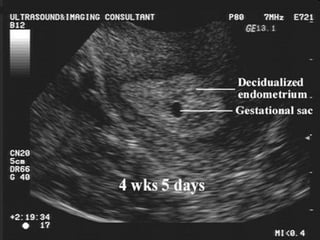

When you find gestational sac??

Dr.Basma ,FM,SCU,2012-2013

True gestational sacTrue gestational sac must bemust be differentiated fromdifferentiated from

pseudo sacpseudo sac

 Embryonic Vesicle (Primary yolk sac

 Round or oval.

 Double ring )Ring of decidualized

endometrium.

 Fundal or mid-portion of the uterus.

 May occasionally implant low down in the

uterine cavity.